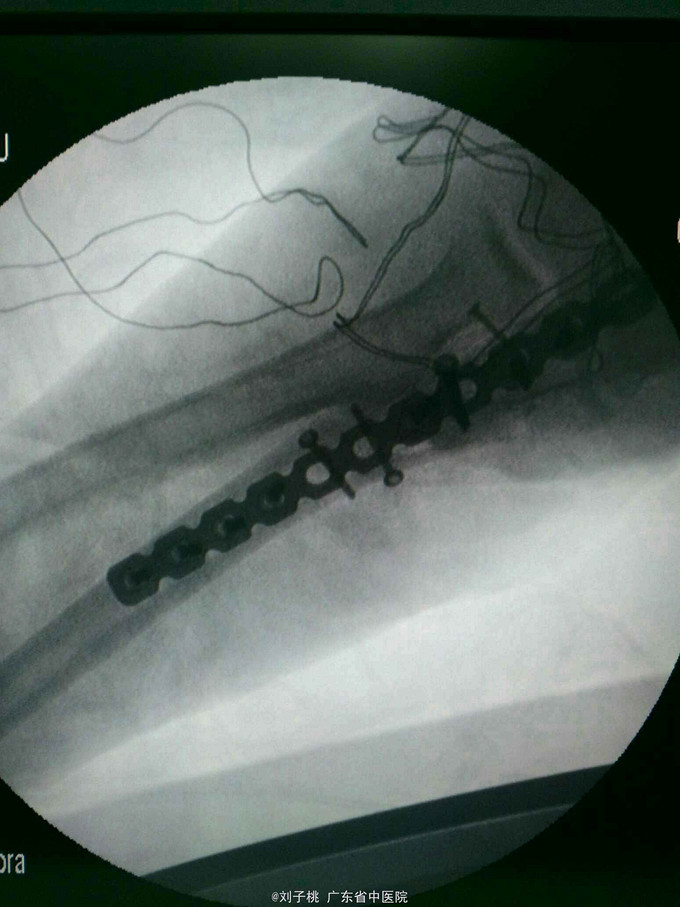

#骨科科室play#右肘开放性孟氏骨折

右肘开放性孟氏骨折,尺神经断裂,急诊行清创内固定加神经修复。

1.开放骨折,一期内固定有无违反原则? 2.尺神经吻合有什么技巧,用几号线,多少针?预后怎样?